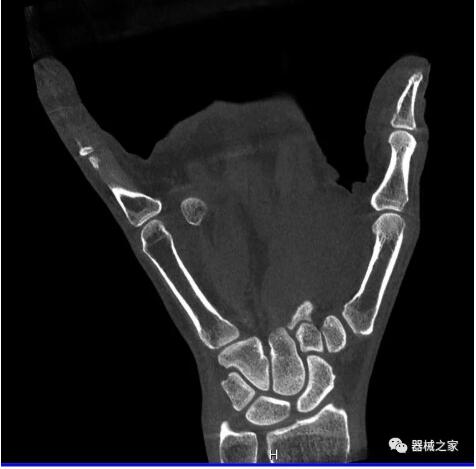

以下是這些“特立獨(dú)行”的CT所拍出來的圖像:

而患者站著做足部或者踝部做CT檢查還有個(gè)好處是,可以檢查患者在負(fù)重的情況下,骨關(guān)節(jié)的真實(shí)情況,而躺著做CT掃查時(shí)未必能看出來。負(fù)重CT掃查特別是對于受傷的運(yùn)動員或者舞蹈員來說意義更大,能夠更準(zhǔn)確地評估傷情,幫助他們盡早復(fù)原。